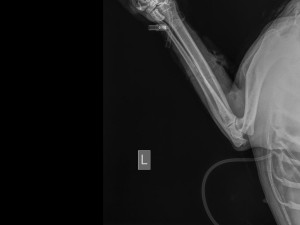

Jedna kulka zasáhla hrudník, svezla se po hrudní kosti a nezasáhla tak orgány. Další tři pak packu, kterou zřejmě budou muset amputovat.